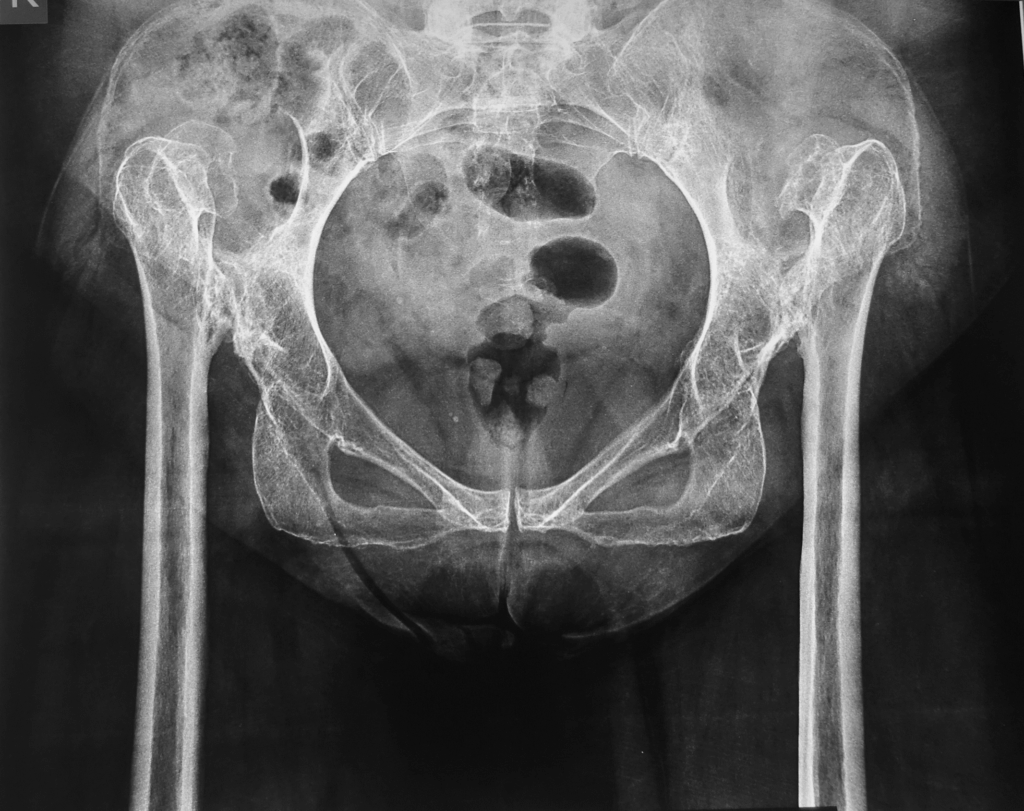

Υψηλό Συγγενές Εξάρθρημα του Ισχίου

To συγγενές εξάρθρημα του ίσχιου είναι μια κατάσταση όπου ο ασθενής γεννήθηκε με δυσπλασία και έκτοπη θέση της άρθρωσης του ισχίου. Μια παραμελημένη τέτοια κατάσταση που δεν αντιμετωπίστηκε στα πρώϊμα βρεφικά στάδια προκαλεί σημαντικά προβλήματα στην ενηλική ζωή.

Η εξειδικευμένη αντιμετώπιση της δυσπλασίας αυτής στους ενήλικες αποτελεί εξαιρετικά απαιτητική επέμβαση που λίγα κέντρα στην Ελλάδα και το εξωτερικό διαθέτουν σημαντική εμπειρία.